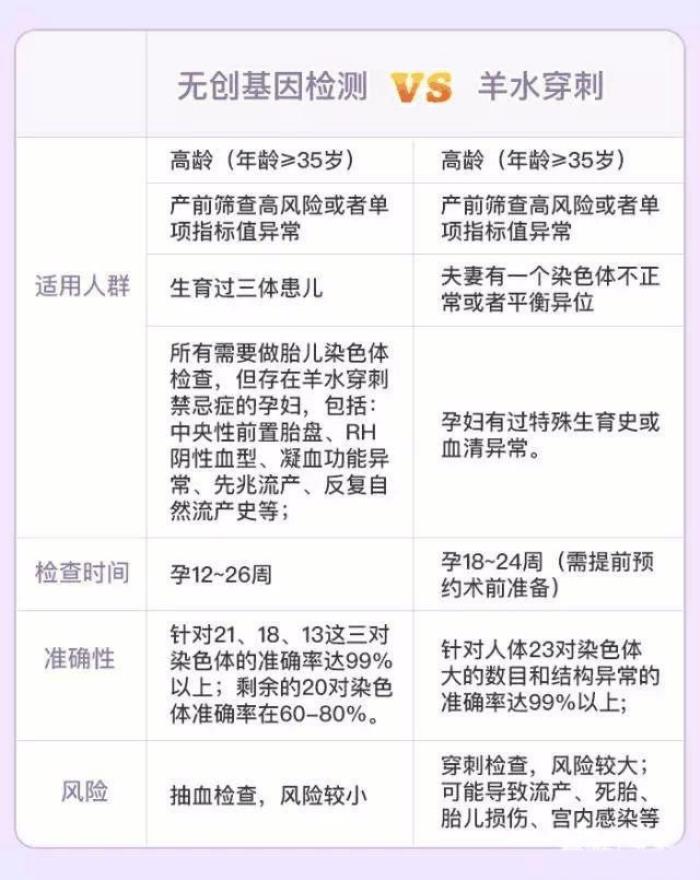

检查三、无创DNA检测或羊水穿刺

检查时间:时间不等,具体咨询医生

遇到需要进一步复查的孕妈,会在这两者间纠结,到底选择哪个?

当然,这两项检查各有优缺点,如下图,相比来说,羊水穿刺 针对23对染色体的准确率都是99%,但是因为要抽羊水出来,风险大;无创DNA 只有3对染色体是99%的准确率,其他染色体的准确率要低些,但是只抽5ml血,风险小很多。

因此,孕妈们可以根据自己的情况,咨询医生的建议再进行选择。